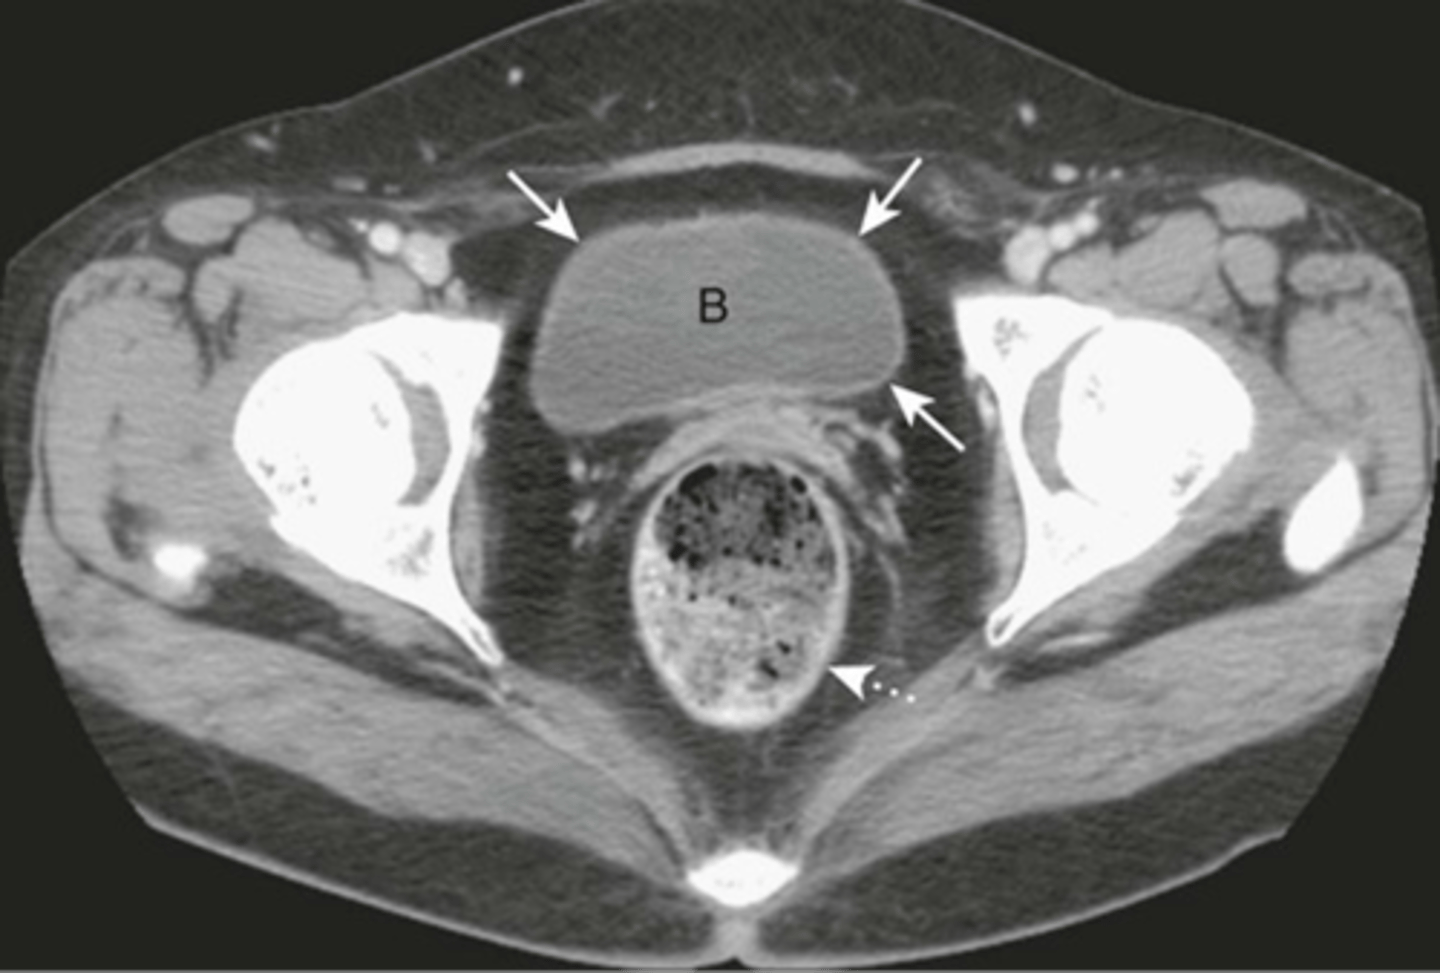

Normal bladder CT